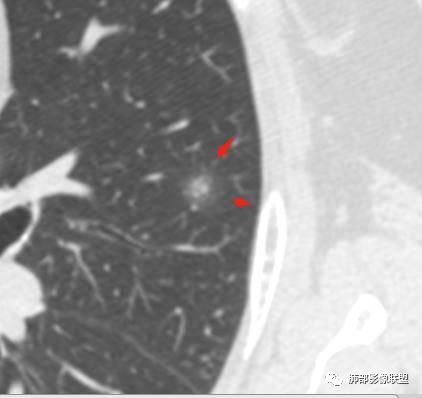

我怎么感觉支气管是通的,周围的晕又比较软,我考虑炎性病变,隐球菌可能大(如下图)

南边:首先自然是看GGO的边界如何?清楚吗?哞:边界模糊南边:其次内部的支气管如何?Coke with ice:清。可见穿行。哞:有通过,也有阻塞吧M-Imaging :进入一半南边:常规的窗宽窗位边界好像不清

也有点散南边:我觉得支气管走形自然,远端稍扩张M-Imaging :略有扩张南边:倾向于炎性宇宙星空:支持M-Imaging :腺癌的GGO,非常清晰的结果:

1.隐球菌病灶往往是实性密度结节为主伴周边边界不清楚的晕,有时可见晕内细软毛刺。

3.病灶内支气管安然无恙隐球菌病灶更加多见